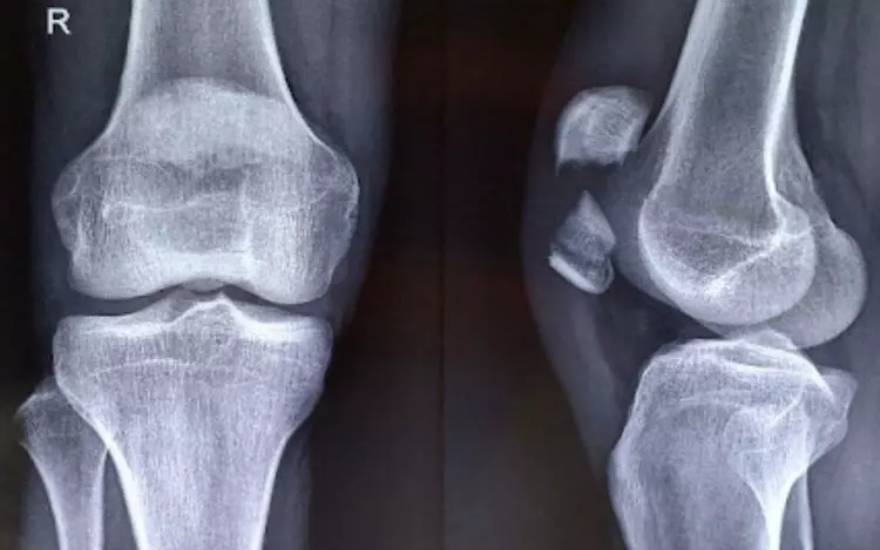

슬개골(Patella)은 무릎 관절 앞부분을 보호하는 뼈로, 무릎을 펴거나 굽힐 때 지렛대 역할을 하여 다리의 움직임과 균형 유지를 돕는 핵심적인 부위입니다. 슬개골 골절은 이 뼈에 금이 가거나 여러 조각으로 부서지는 심각한 상태를 의미합니다. 골절이 발생하면 무릎 관절의 가동 범위가 급격히 줄어들며, 일상적인 활동에 큰 통증과 제약을 유발합니다.

무릎 관절의 슬개골 구조 이미지